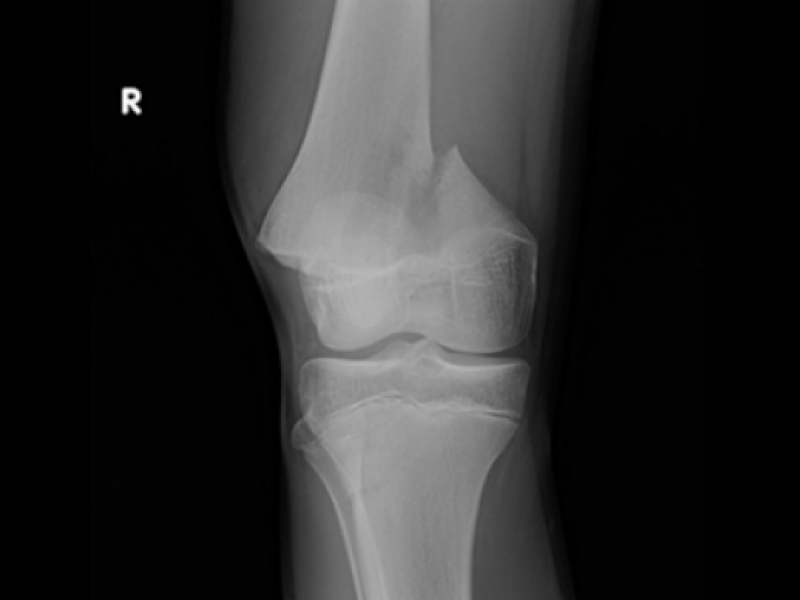

Back to Basics: A Case of Traumatic Knee Pain By Dr. Ozair